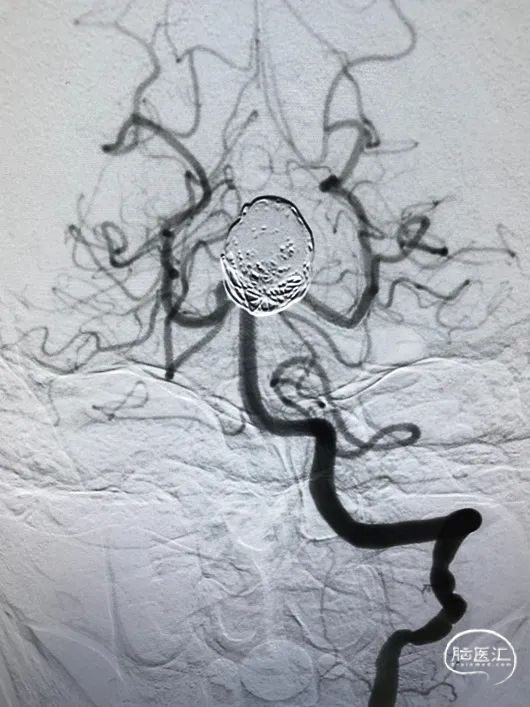

术前3D成像

3D成像 动脉瘤大小

基底动脉上段3.1mm P1段2.5mm 动脉瘤最大径22.66*24.68mm。

3.25*20mm Pipeline

eV3 25mm*50cm弹簧圈

支架打开后可见造影剂滞留

术后即刻影像

术后工作位造影

eV3 25mm*50cm弹簧圈2枚,22mm*50cm弹簧圈2枚,16mm*40cm1枚,14mm*40cm2枚。

瘤囊+瘤颈处弹簧圈疏松填塞